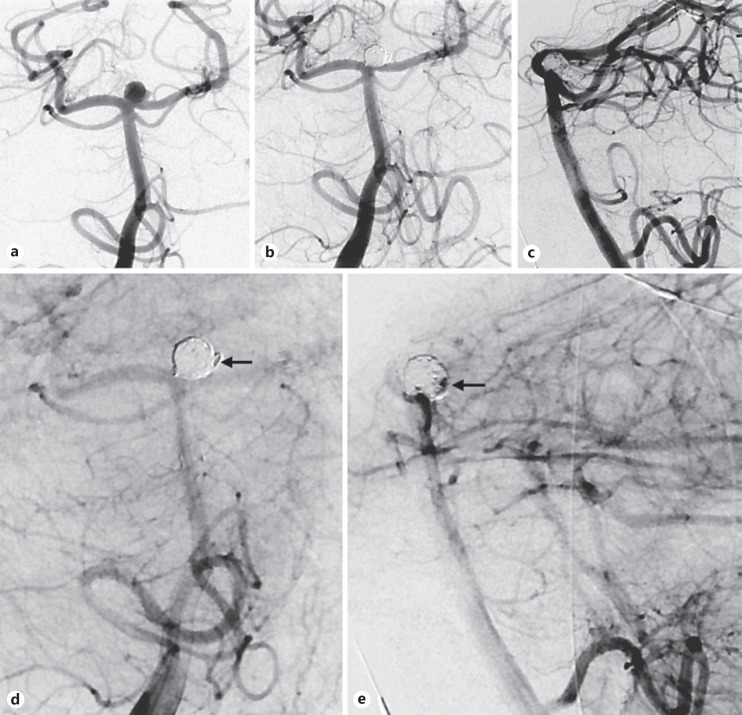

In 2 cases, a suboptimal angiographic result was achieved after utilizing a dedicated intracranial stent to treat symptomatic intracranial stenoses. Despite initially modest angiographic results, significant restenosis occurred in both cases requiring angioplasty. Along with his senior authors' institutional preference, the junior author now defers to the utilization of balloon-mounted coronary stents for intracranial stenting, which exert a higher radial force and potentially superior wall apposition (Fig. 1).

Fig. 1.

Anteroposterior view of a recurrently symptomatic severe left M1 stenosis despite maximal medical therapy (a). In the context of significant proximal vessel tortuosity, a 150-cm microcatheter was used to transverse the lesion and thus a dedicated intracranial stent was deployed to treat the lesion (b, anteroposterior view after stenting). The patient did have a femoral pseudoaneurysm post procedure. Three months later, severe in-stent stenosis was seen (c, anteroposterior view of left internal carotid artery injection). Utilizing a stiff Amplatz wire, carotid tortuosity was straightened and a shorter, less compliant coronary system was used for successful angioplasty. Illustrative pre- (d) and postangiographic views (e) after utilizing a balloon-mounted coronary stent for symptomatic M1 stenosis later in this series.

“Getting out of trouble” and even avoiding “getting into trouble” is a battle that one need not fight on one's own, particularly in high-volume, experienced centers with resourceful partners. Complex aneurysms and flow diversion cases were initially evaluated with diagnostic angiography alone, with treatment staged in unruptured cases to meticulously evaluate angiography, size anticipated constructs, and potentially review the approach with endovascular partners. In 2 technical complication cases, senior partners were able to cross a carotid occlusion without difficulty or complication. At our institution, the stroke neurology service harbors an aggressive stance toward symptomatic carotid occlusion; as such, endovascular practitioners have uniquely considerable experience crossing challenging, chronic calcified occlusions. In recognizing this unique experience, a low threshold was maintained in seeking their assistance. In contrast, in 2 cases of challenging intracranial stenoses/occlusions, soliciting their input may have led to consideration of higher radial force coronary stents, potentially improving initial and long-term angiographic results (Fig. 1) [9, 10].